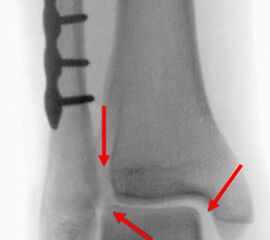

Seit einer Untersuchung von Nelson und Jensen aus dem Jahre 1940 wird allgemein akzeptiert, dass die Indikation zur Osteosynthese des Tibiahinterkantenfragments nur dann besteht, wenn die Größe mehr als ein Drittel (nach zahlreichen Autoren auch ein Viertel) der Gelenkfläche beträgt (Abbildung 15) 25. Dieses bis heute allgemeinakzeptierte Vorgehen basiert auf der Beobachtung von lediglich acht unterschiedlich versorgten Patienten. Seither gibt es keine weiteren klinischen Studien, die dieses Vorgehen stützen. Mittlerweile gibt es allerdings zunehmend Hinweise, dass bei der Versorgung des posterioren Malleolus viele andere Faktoren eine wichtige Rolle spielen 26. Da an der Tibiahinterkante das Lig. tibiofibulare posterius ansetzt (Abbildung 16), wird durch die offene Reposition und Stabilisierung die Integrität und die physiologische Spannung der hinteren Syndesmose rekonstruiert (Abbildung 17). Dies ist entscheidend für die anatomische Reposition der Fibula in der Tibiainzisur.

Gardner et al. konnten beispielsweise zeigen, dass die offene anatomische Reposition der Tibiahinterkante der Stabilisierung mittels Stellschraube überlegen war und gleichzeitig mit einer geringeren Rate an postoperativen Fehlstellungen der Fibula in der CT-Kontrolle einherging 2728. Aus Sicht der Autoren ist prinzipiell die Stabilisierung über eine direkte Reposition indiziert, wenn die Größe des Fragmentes dies erlaubt. Bei gleichzeitigem Vorliegen einer Fraktur des lateralen und/oder medialen Malleolus sollte zunächst die Versorgung der des Tibiahinterkantenfragments erfolgen. Dies erlaubt die radiologische Kontrolle der Reposition und Osteosynthese-Lage, welche durch eine zuvor aufgebrachte Fibula-Platte häufig erschwert ist 29. Dafür werden die Patienten in Seitenlage gelagert. Dies erlaubt die direkte Versorgung der posterioren Malleolusfraktur über einen posterolateralen Zugang 30. Das sehr kräftige Periost wird im Frakturverlauf inzidiert und aus den Frakturspalt entfernt, so kann eine anatomische Reposition erfolgen. Entsprechend der Fragmentgröße erfolgt entweder die Versorgung mittels Drittelrohrplatte in Antiglide-Technik oder eine Zugschraubenosteosynthese. Die Versorgung der Fibula-Fraktur gelingt über den gleichen Zugang. Zur Versorgung des medialen Malleolus wird der Patient auf den Rücken umgelagert. Dies kann bei entsprechender Vorbereitung ohne erneutes steriles Abdecken erfolgen. Durch dieses Vorgehen konnte im eigenen Kollektiv die Notwendigkeit einer Stabilisierung der Syndesmose mit Stellschraube/Tight Rope deutlich reduziert werden.